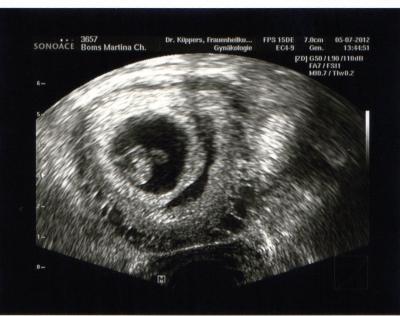

War heute beim Doc. Würmchen geht es gut. Es ist 1,3 cm groß und das Herz hat weiterhin geblubbert. Nun hab ich auch meinen Mutterpass. *Freu*

Bild zu Komme vom FA - Forum für Februar - Mamis